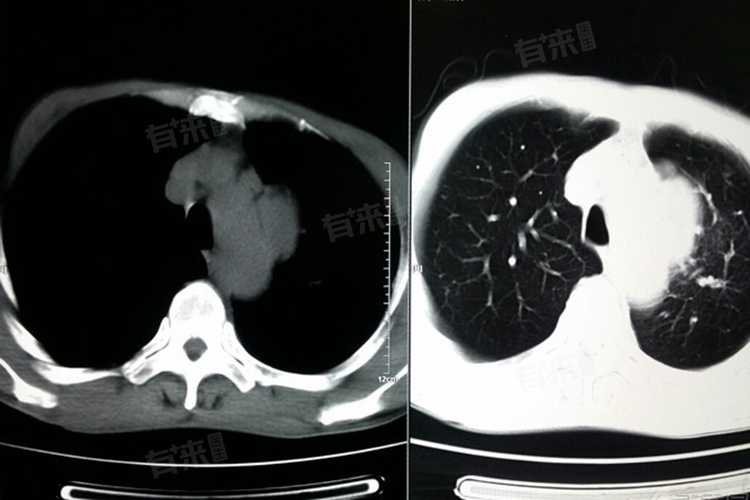

诊断中央型肺癌需综合运用多种方法,胸部影像学检查是重要手段,胸部X线可发现靠近肺门的肿块阴影,但对于较小的肿瘤可能漏诊。胸部CT则更为精准,能清晰显示肿瘤的位置、大小、形态,以及与周围组织的关系,还可发现肺门及纵隔淋巴结肿大情况。支气管镜检查在中央型肺癌诊断中具有独特优势,可直接观察支气管内病变,获取病变组织进行病理活检。